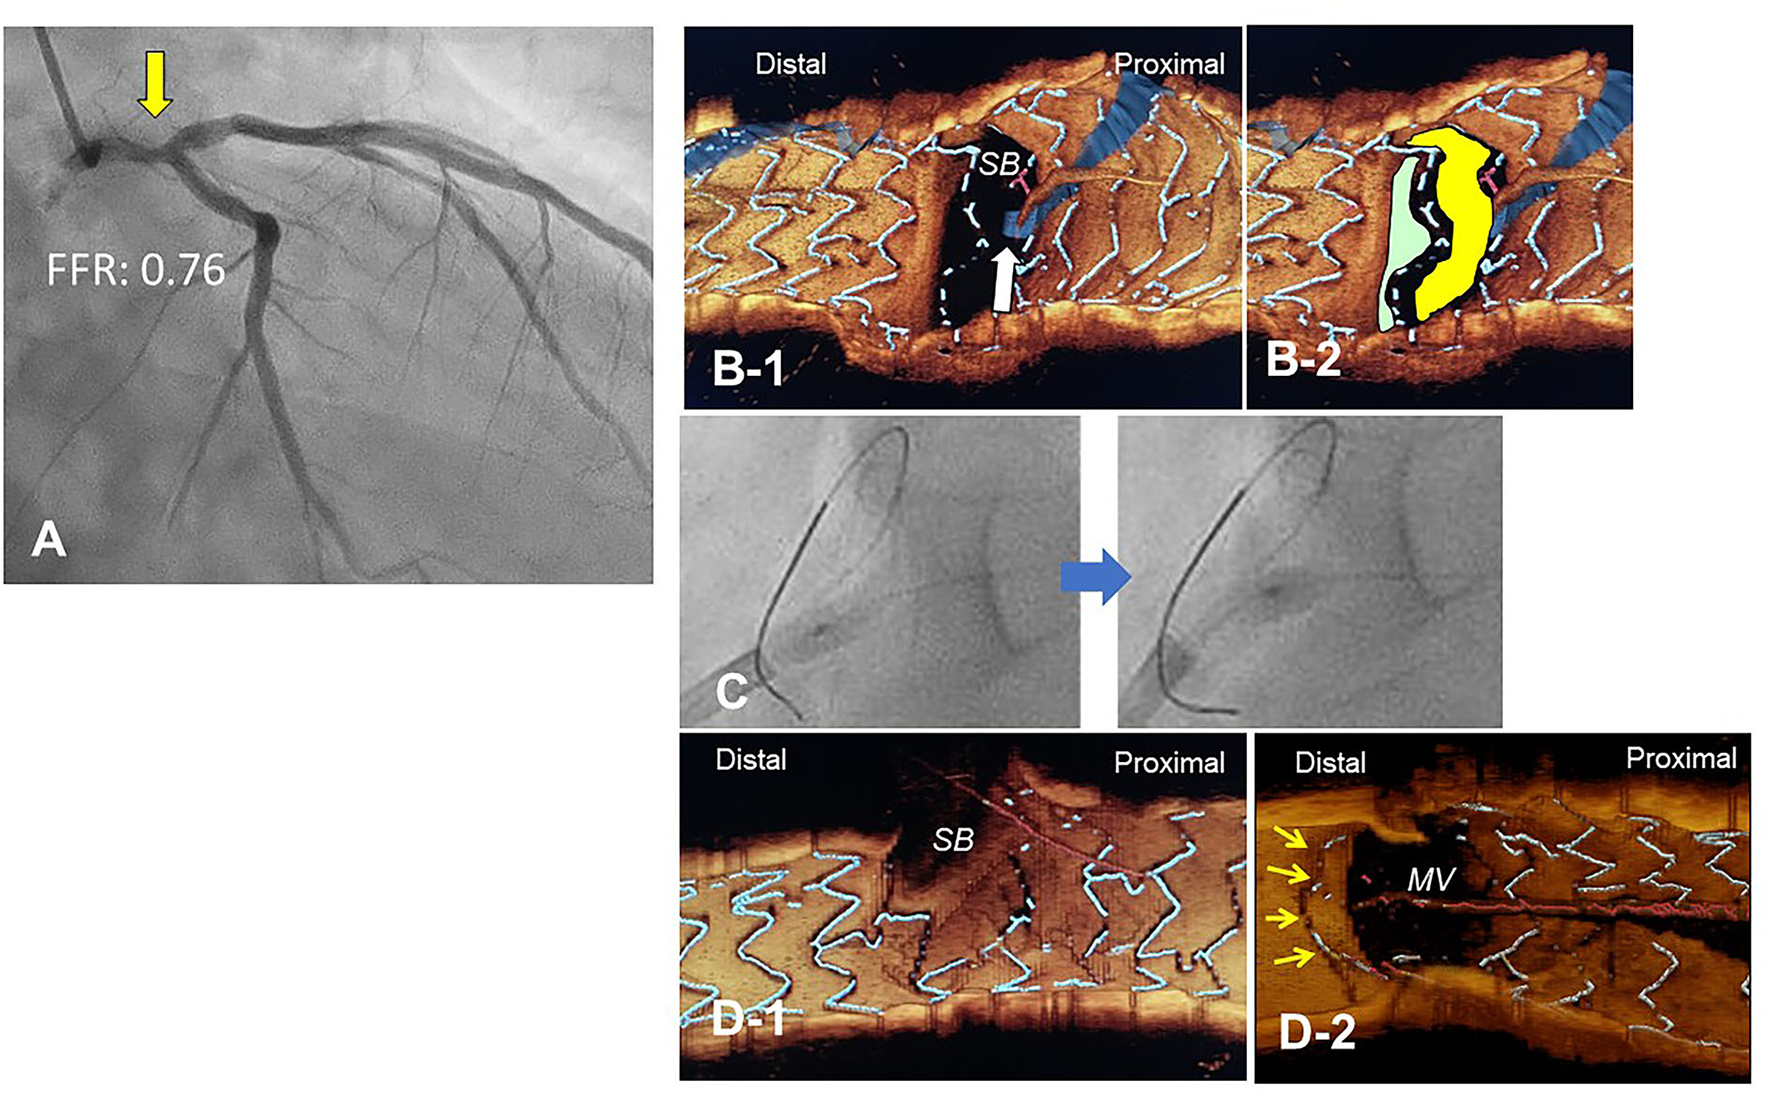

Figure 10

Push-fold method for complete removal of jailing struts in the side branch (SB) ostium. A 78-year-old man with Medina 1-1-0 lesion in LM bifurcation with a drop of fractional flow reserve (FFR) of 0.76 (A). After cross-over stenting from LM to LAD with a Xience Alpine 3.5/28 mm stent and subsequent proximal optimization in LM with a 4.5 mm balloon, guidewire recrossing to the distal cell (green cell) was difficult even after several attempts and finally crossed to the proximal cell (yellow cell, white arrow) (B). For the removal of the jailing struts in the SB ostium, an inflated 2.5/4 mm balloon was pushed from LM to LCX (C). Final 3-D OCT demonstrated complete removal of the jailing struts in the SB ostium (D-1, pull back from main vessel [MV]), and the jailing strut folded toward the carina (D-2, pull back from SB).

The most contemporary concept of 3D OCT-guided SB treatment is based on the model of jailing strut configuration and guidewire recrossing cells. In the LF type, a higher success rate of optimal distal wiring can be achieved under 3D OCT guidance, which leads to optimal SB dilation (Figure 9). In the LC type, distal-cell wiring does not always reduce ISA (Figure 9). First, a more aggressive POT is used, which provides greater expansion of the bifurcation core and decreases the number of jailing struts. Changing to the NLJ type without SB compromise allows the SB to remain undilated. More protrusion into the SB ostium of the far-distal cell, which is neighboring distally to the distal cell with a link connection, allows the guidewire to recross to the far-distal cell without a link connection, leading to more SB ostial expansion. When these results are not obtained, guidewire recrossing to the cell that occupies most of the SB ostium and subsequent SB dilation are also reasonable treatments. Another cutting-edge treatment is the push-fold method, in which the guidewire is intentionally crossed in the proximal cell, and an inflated balloon pushes the jailing struts away in the direction of the SB ostium (34, 35) (Figure 10). In the NLJ type, SB treatment can be deferred unless severe compromise occurs (Figure 9).